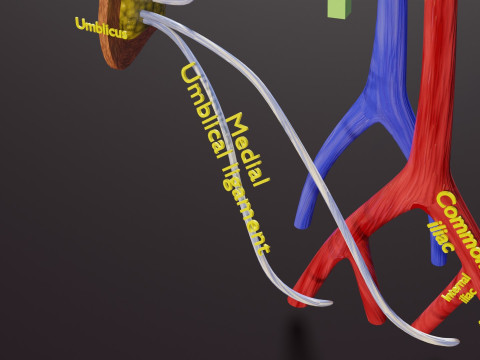

The model meshes include adult circulation versus circulation in Tetralogy of Fallot (TAF), arrow labels and text labels. The blood flow in a patient with Tetralogy of Fallot is outlined in this model. To contrast it to normal blood circulation a separate model of normal circulation is included. The Tetralogy of Fallot (OVER RIDING OF AORTA, PUL STENOSIS, VENTRICULAR SEPTAL DEFECT, RIGHT VENTRICULAR HYPERTROPHY), fossa, ligament teres , venosus, and arteriosus are duly depicted with proper labelling and blood flow directional arrows. Excellent model for teaching, demonstration and knowlegde of human body. The models include both procedural and image textures blend files separately. The texture file include diffuse, roughness and normal png and jpeg based on non overlapping UV maps.